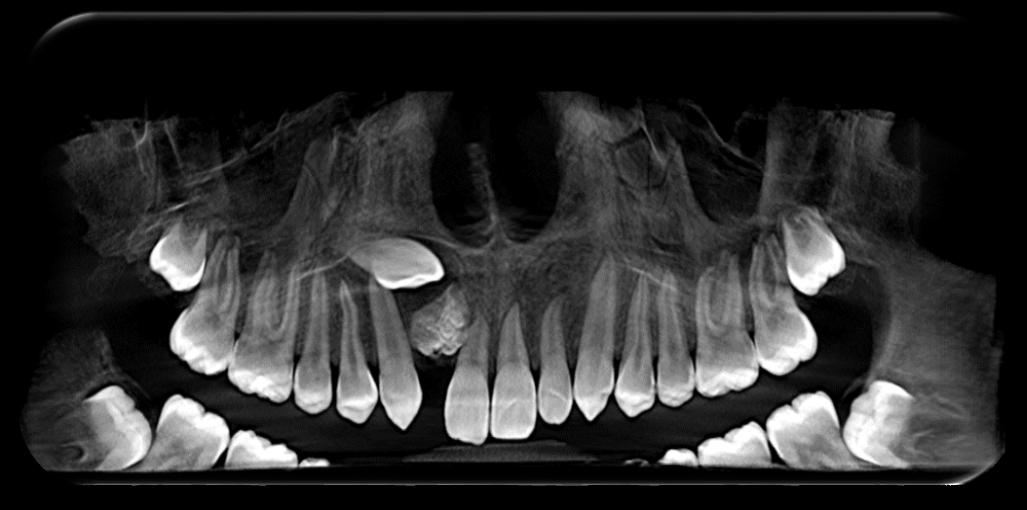

DISCUSIÓN

Tomando en cuenta nuestro caso clínico, los estudios histopatológicos determinaron que estamos frente a un proceso inflamatorio crónico inespecífico con fibrosis marcada, su extirpación fue exitosa sin ningún tipo de complicaciones dentro de la cirugía y del postoperatorio; Zambuzzi et al reportaron en un estudio que la hidroxiapatita natural de hueso bovino promueve un ambiente adecuado para la adhesión, proliferación y diferenciación de osteoblastos, lo cual lleva a una adecuada resolución del hueso (3); desde otro ángulo Chiapasco A. et al comparan la regeneración de cavidades quísticas mediante esponjas de colágeno (mantenedoras del espacio y estabilizadoras) y hueso liofilizado desmineralizado de cadáver; no encontraron diferencias estadísticamente significativas entre ambos grupos a los dos años, lo que confirma que en cualquier caso se presentará buena cicatrización ósea posterior a la quistectomías, al utilizar materiales aloplásticos, injertos o la propia formación ósea espontánea; ambos procedimiento utilizados en nuestro paciente (4).

RIIS UNIVALLE. Jul-Dic. 17(43), 2022; ISSN: 2075-6208 105 Aplicación de biomateriales post exeresis en un quiste inflamatorio radicular Adrián-Hurtado y cols.

Figura 9. Obtención del Sticky bone (SB), mezcla del A- PRF más el hueso bovino.

Hernández R. et al concuerdan con que el uso de injertos óseos es un método seguro, simple, eficaz y que además el odontólogo puede emplear para diversos defectos óseos alveolares, siempre y cuando sea considerado su sitio de colocación ya que esto influye directamente con el éxito del tratamiento. En sus tres reportes de casos pudo evidenciar que el uso de injertos promovió su buena oseointegración y presentó un alto nivel de biocompatibilidad, además ninguno de estos tres autores difiere en sus opiniones (5) (9) (10).

Cuando existe pérdida de tejido óseo extenso es importante utilizar biomateriales que produzcan osteoconducción, osteoinducción y osteogénesis, puesto que estos tienen la capacidad de estimular

REFERENCIAS BIBLIOGRÁFICAS

la formación ósea de una manera más rápida; dependiendo del tipo de material veremos que la formación ósea será más adecuada, tanto en volumen como en calidad; con esto no tratamos de indicar que la recuperación fisiológica no será buena, sino que esta tarda más tiempo, en contraste con el uso biomateriales y el aumento de densidad ósea; debido a la extensión de la cavidad, el relleno de la misma con el Sticky bone y cubrir con una membrana de pericardio porcino, se espera que cumplan la función osteoconductora en la cavidad. Basándonos en los estudios y revisiones recientes, esperamos buenos resultados en nuestros pacientes, debido a que el tiempo de neoformación dura aproximadamente 6 a 8 meses, por lo cual aún se encuentra en proceso.

1. García, A., Buljadón, A., & Rodríguez, A. (Febrero de 2015). Lesiones periapicales. Diagnóstico y Tratamiento. Avances en Odontoestomatología, XXXI(1), 31-42. Recuperado el 9 de Juio de 2018, Doi: https://doi.org/10.4321/S0213-12852015000100005

2. Swennen G, Dempf R, Schliephake H. Cranio-facial distraction osteogenesis: a review of the literature. Part II: Experimental studies. Int J Oral Maxillofac Surg. 2002 Apr; 31(2): 123-35. doi: https://doi.org/10.1054/ijom.2002.0225

3. Rebolledo M, Harris J, Higgins E, Molinares L. Cicatrización y regeneración ósea de los maxilares después de una quistectomía: reporte de un caso y revisión de la literatura. Univ Odontol. 2011 Jul-Dic; 30(65): 71-78 Recibido para publicación: 15-05-2011 Correcciones recibidas: 09-09-2011 Aceptado para publicación: 11-10-2011 Disponible en http://www.javeriana.edu.co/

4. Zambuzzi WF, Ferreira CV, Granjeiro JM, Aoyama H. Biological behavior of pre-osteoblasts on natural hydroxyapatite: a study of signaling molecules from attachment to differentiation. J Biomed Mater Res. 2011 May; 97(2): 193-200. Epub 2011 Mar 10. Doi.10.1002/jbm.a.32933 https://doi. org/10.1002/jbm.a.32933

5. Chiapasco M, RossiA, Motta JJ, Crescentini M. Spontaneous bone regeneration after enucleation of large mandibular cysts: a radiographic computed analysis of 27 consecutive cases. J Oral Maxillofac Surg. 2000 Sep; 58 (9): 942-8. Discussion 949. Doi https://doi.org/10.1053/joms.2000.8732

6. Edgar Eduardo Serrano Mejía Trabajo de grado para otorgar el título de Odontólogo Director Nohora Camila Rúgeles Páez Esp. Implantología oral y reconstructiva Universidad Santo Tomás, Bucaramanga División de Ciencias de la Salud Faculta de Odontología 2020. http://hdl.handle. net/11634/20496

7. Block MS. The processing of xenografts will result in different clinical responses. Journal of Oral and Maxillofacial Surgery 2018. Doi. 10.1016/j.joms.2018.10.004

8. Johnson, B., Fayad, M., & Witherspoon, D. (2011). Cirugía Perirradicular. En K. Hargreaves, & S. Cohen, Vías de la pulpa (págs. 720-755). Barcelona, España: Elsevier Mosby. Doi. https://doi. org/10.1016/B978-0-323-06489-7.00021-7

9. Morales, D., & Vila, D. (2016). Regeneración ósea guiada en Estomatología. Revista Cubana de Estomatología, LIII(1), 67-83. Recuperado el 17 de Julio de 2018, de http://scielo.sld.cu/scielo. php?script=sci_arttext&pid=S0034-75072016000100008

10. Rebolledo, M., Harris, J., Higgins, E., & Molinares, L. (2011). Cicatrización y regeneración ósea de los maxilares después de una quistectomía: reporte de caso y revisión de la literatura. Universitas Odontológica, 30(65), 71-78. Obtenido de http://www.javeriana.edu.co/universitasodontologica

RIIS UNIVALLE. Jul-Dic. 17(43), 2022; ISSN: 2075-6208 106 Aplicación de biomateriales post exeresis en un quiste inflamatorio radicular Adrián-Hurtado y cols.

DOI: https://doi.org/10.52428/20756208.v17i43.390

Inclusión dentaria por un odontoma compuesto

Dental inclusion by a compound odontoma

Javier Adrian Burgos 1. Francis Daniela Argandoña Ortiz2. Gabriela Adriana Lara León3

1Medico cirujano, Cirujano Dentista, Esp. En Cirugía Bucal, Msc. En Implantología Oral, Docente Univalle Sub- Sede La Paz jadrianb@univalle.edu

2 Estudiante de la Carrera de Odontología, Universidad Privada del Valle La Paz, aof2015031@est.univalle.edu